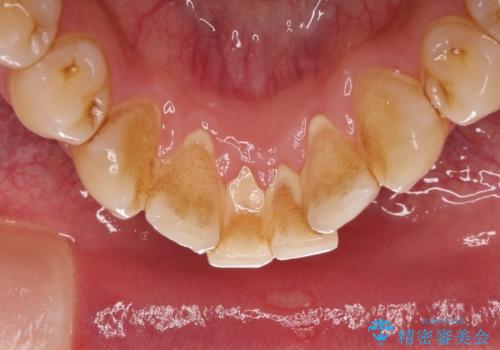

茶渋による着色と下の前歯の裏側のべったり歯石

コーヒーやお茶をよく飲む患者様で、その影響か全体的に茶渋が見られました。

下の前歯は少しがたつきがあるため、歯石がたまりやすいように見られます。

着色落としをメインに歯石も落とすためPMTC(エアフロー)にて施術いたしました。